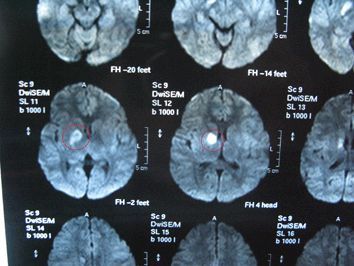

任何人:你看这是片子

任何人:

#冷风落(父):他做的话,成功率是多少

任何人:百分之九十五以上没问题

#冷风落(父):他看了一眼众人,发现都在看他叹了口气说,医生说,他现在抑郁症加重了,中度抑郁症,还有点自闭,只能先开点药压制,在病发的时候给他服下一粒还有就是他现在情况还算好就是这个肿瘤的位置不好办,只能找他了

#冷风落(父):这是片子和药

#冷风落(父):

千田灵子(冷母):你妹妹脑里长了个肿瘤,但是太小了,压到了神经导致的头痛,抑郁症也就加重了现在是中度抑郁症还有点自闭的倾向

千田灵子(冷母):医生给我们的建议是出国治疗找到鬼医圣手——魅